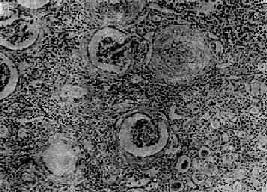

图12-25 慢性肾盂肾炎

有些肾小球毛细血管丛相对正常,肾球囊壁增厚,纤维化,部分肾小管萎缩消失,部分肾小管扩张,腔内有胶样管型;间质纤维组织增生,有大量淋巴细胞等炎细胞浸润